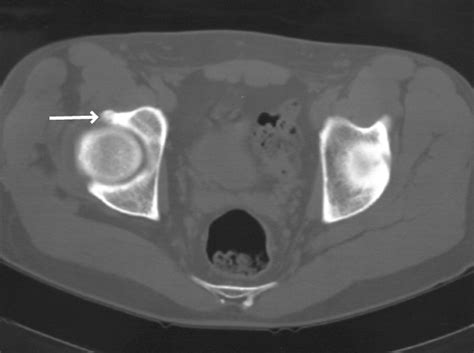

If you suspect you have Cam Impingement Hip, a physical examination is the first step. An orthopedic specialist will perform specific tests, such as the FADIR test (Flexion, Adduction, Internal Rotation), which is designed to reproduce the impingement and pain. Following this, imaging is usually required to confirm the diagnosis.

• X-rays: Standard views help the doctor visualize the shape of the femur and the degree of the bony prominence.

• MRI or MRA: These scans are critical for evaluating the soft tissues, specifically looking for labral tears or cartilage thinning that might have resulted from the impingement.